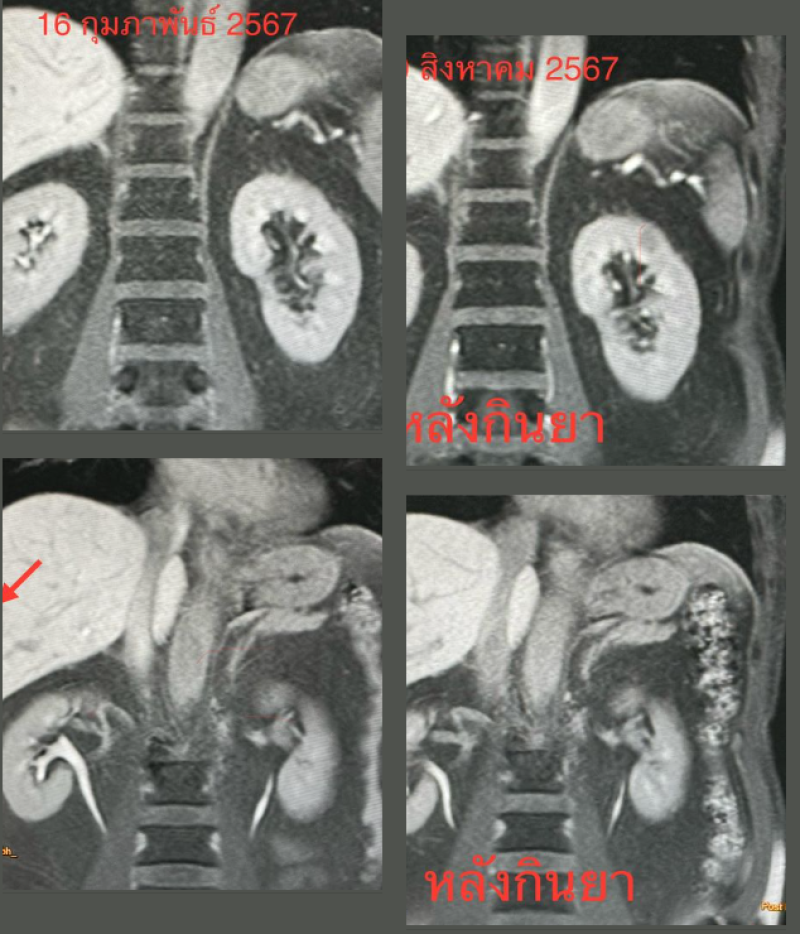

-ทำคลื่นแม่เหล็กไฟฟ้า MRI ของตับพบก้อนขนาด 2.8 × 2.4 × 2.1 ซม.และ 4.5 × 3.1 × 3.3 ซม.ในตับข้างขวา (ดูรูป)

ติดตามคนไข้ 6 เดือนหลังกินยาฆ่าพยาธิ วันที่ 19 สิงหาคม 2567 ไม่ปวดท้อง ไม่มีไข้ กินอาหารได้ เจาะเลือดพบจำนวนเม็ดเลือดขาว 5,620 เซลล์ เป็นเซลล์ชนิด eosinophil 8% (ลดลงเดิม 37%) ติดตามคลื่นแม่เหล็กไฟฟ้า MRI ของตับพบก้อนทั้ง 2 ก้อนในตับข้างขวาขนาดเล็กลงมาก